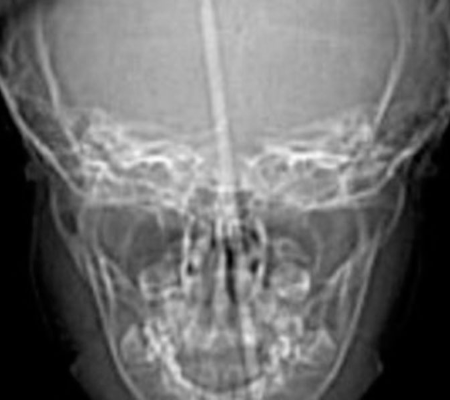

Uma criança de três anos teve a cabeça perfurada por uma agulha de tricô enquanto brincava que era uma fada. Ela estava pulando em cima de uma cama quando se desequilibrou e caiu. O objeto entrou pela boca da menina, perfurou o crânio e atingiu o cérebro.

Ela foi levada às pressas ao hospital, que fica em Utah, nos Estados Unidos, e os médicos descobriram que a agulha atingiu a hipófise e o hipotálamo, regiões responsáveis por hormônios e pela coordenação dos movimentos do corpo.

Por mais que ela estivesse sangrando muito, uma tomografia mostrou que os pequenos vasos sanguíneos dela estavam a salvo. A história da " menina mais sortuda do mundo" virou artigo na revista Journal of Pediatric Otorhinolaryngology Case Reports.